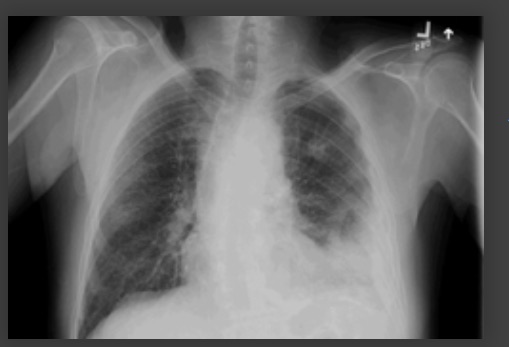

derrame pleural del lado izquierdo

De la colección del Dr. R Light. Usado con autorización